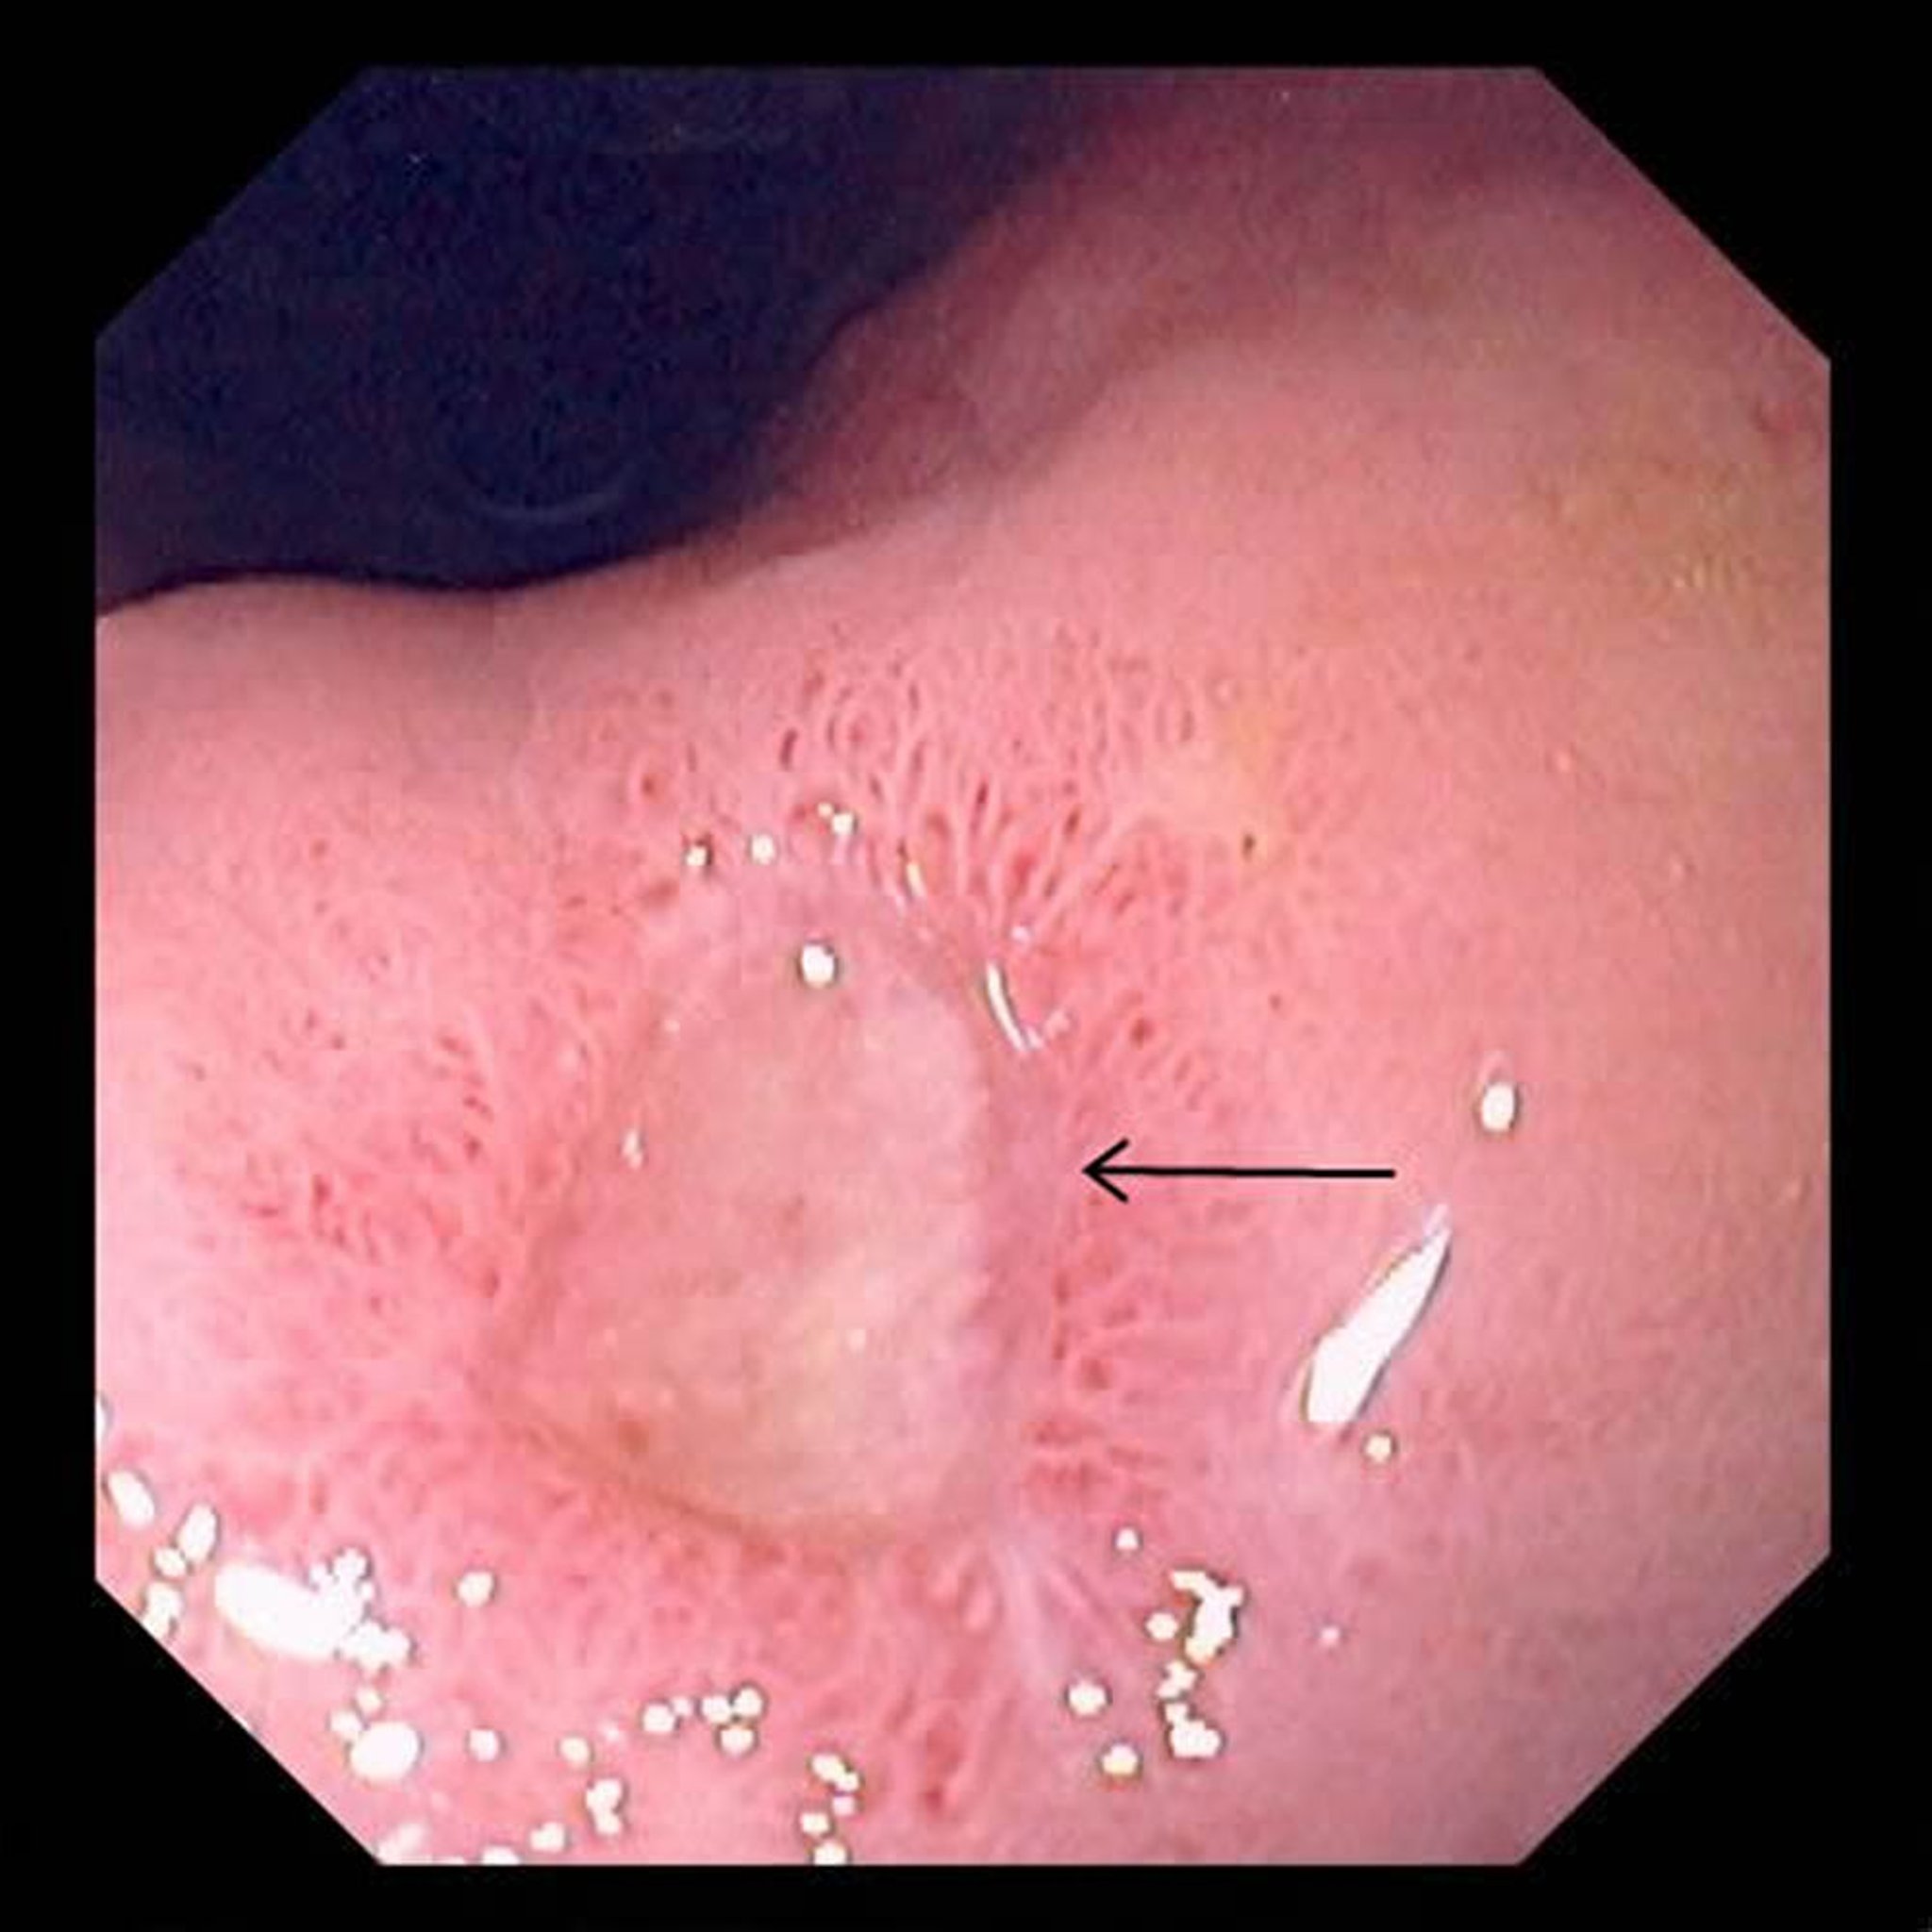

Dieses Foto zeigt ein großes Geschwür (Pfeil) im Magen.

Foto von David M. Martin, MD.